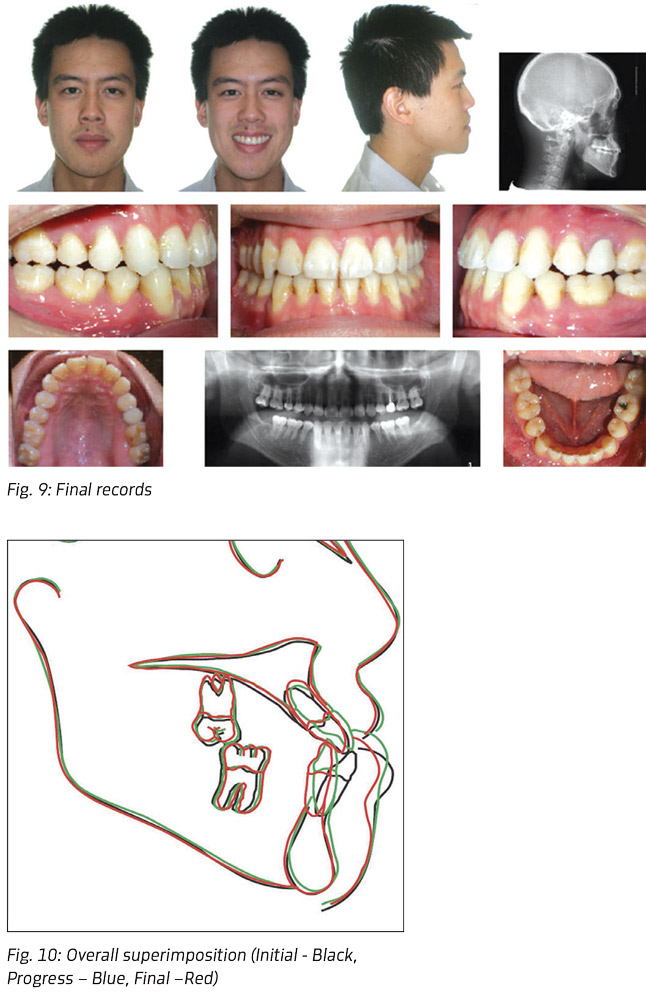

Twenty-one maxillary and mandibular trays were necessary to complete treatment. Buttons were bonded on L7's after the third aligners and bilateral ¼-inch 4.5oz Class II elastics were started. All attachments were removed after completion of aligner 15 because of the patient's wedding. Elastics were continued and the remaining aligners delivered. Buttons were removed after 10.5 months and final records taken (Fig. 9).

Retention included full-coverage 0.040 Trutain retainers for both arches to be worn at night only. The three-month follow-up was unremarkable and the nine-month retainer check revealed a stable occlusion. With no change at the two-year check, the patient was instructed to wear retainers every other night.

Treatment outcomes

The treatment revealed an acceptable facial esthetic and good occlusion. Lateral cephalometric superimpositions (Fig. 10) demonstrate a reduction of the lower-lip prominence as a result of retroclination and retrusion of the mandibular incisors.

Cephalometric measurements showed many measurable changes as well. The dentoalveolar complex showed significant changes in protrusion and angulation of the mandibular incisors: the lower incisors were retracted more than 7mm comparing to the A-Pog line and their angulation reduced by about 17 degrees compared to IMPA. The Wits Appraisal improved positively by 4.2mm.